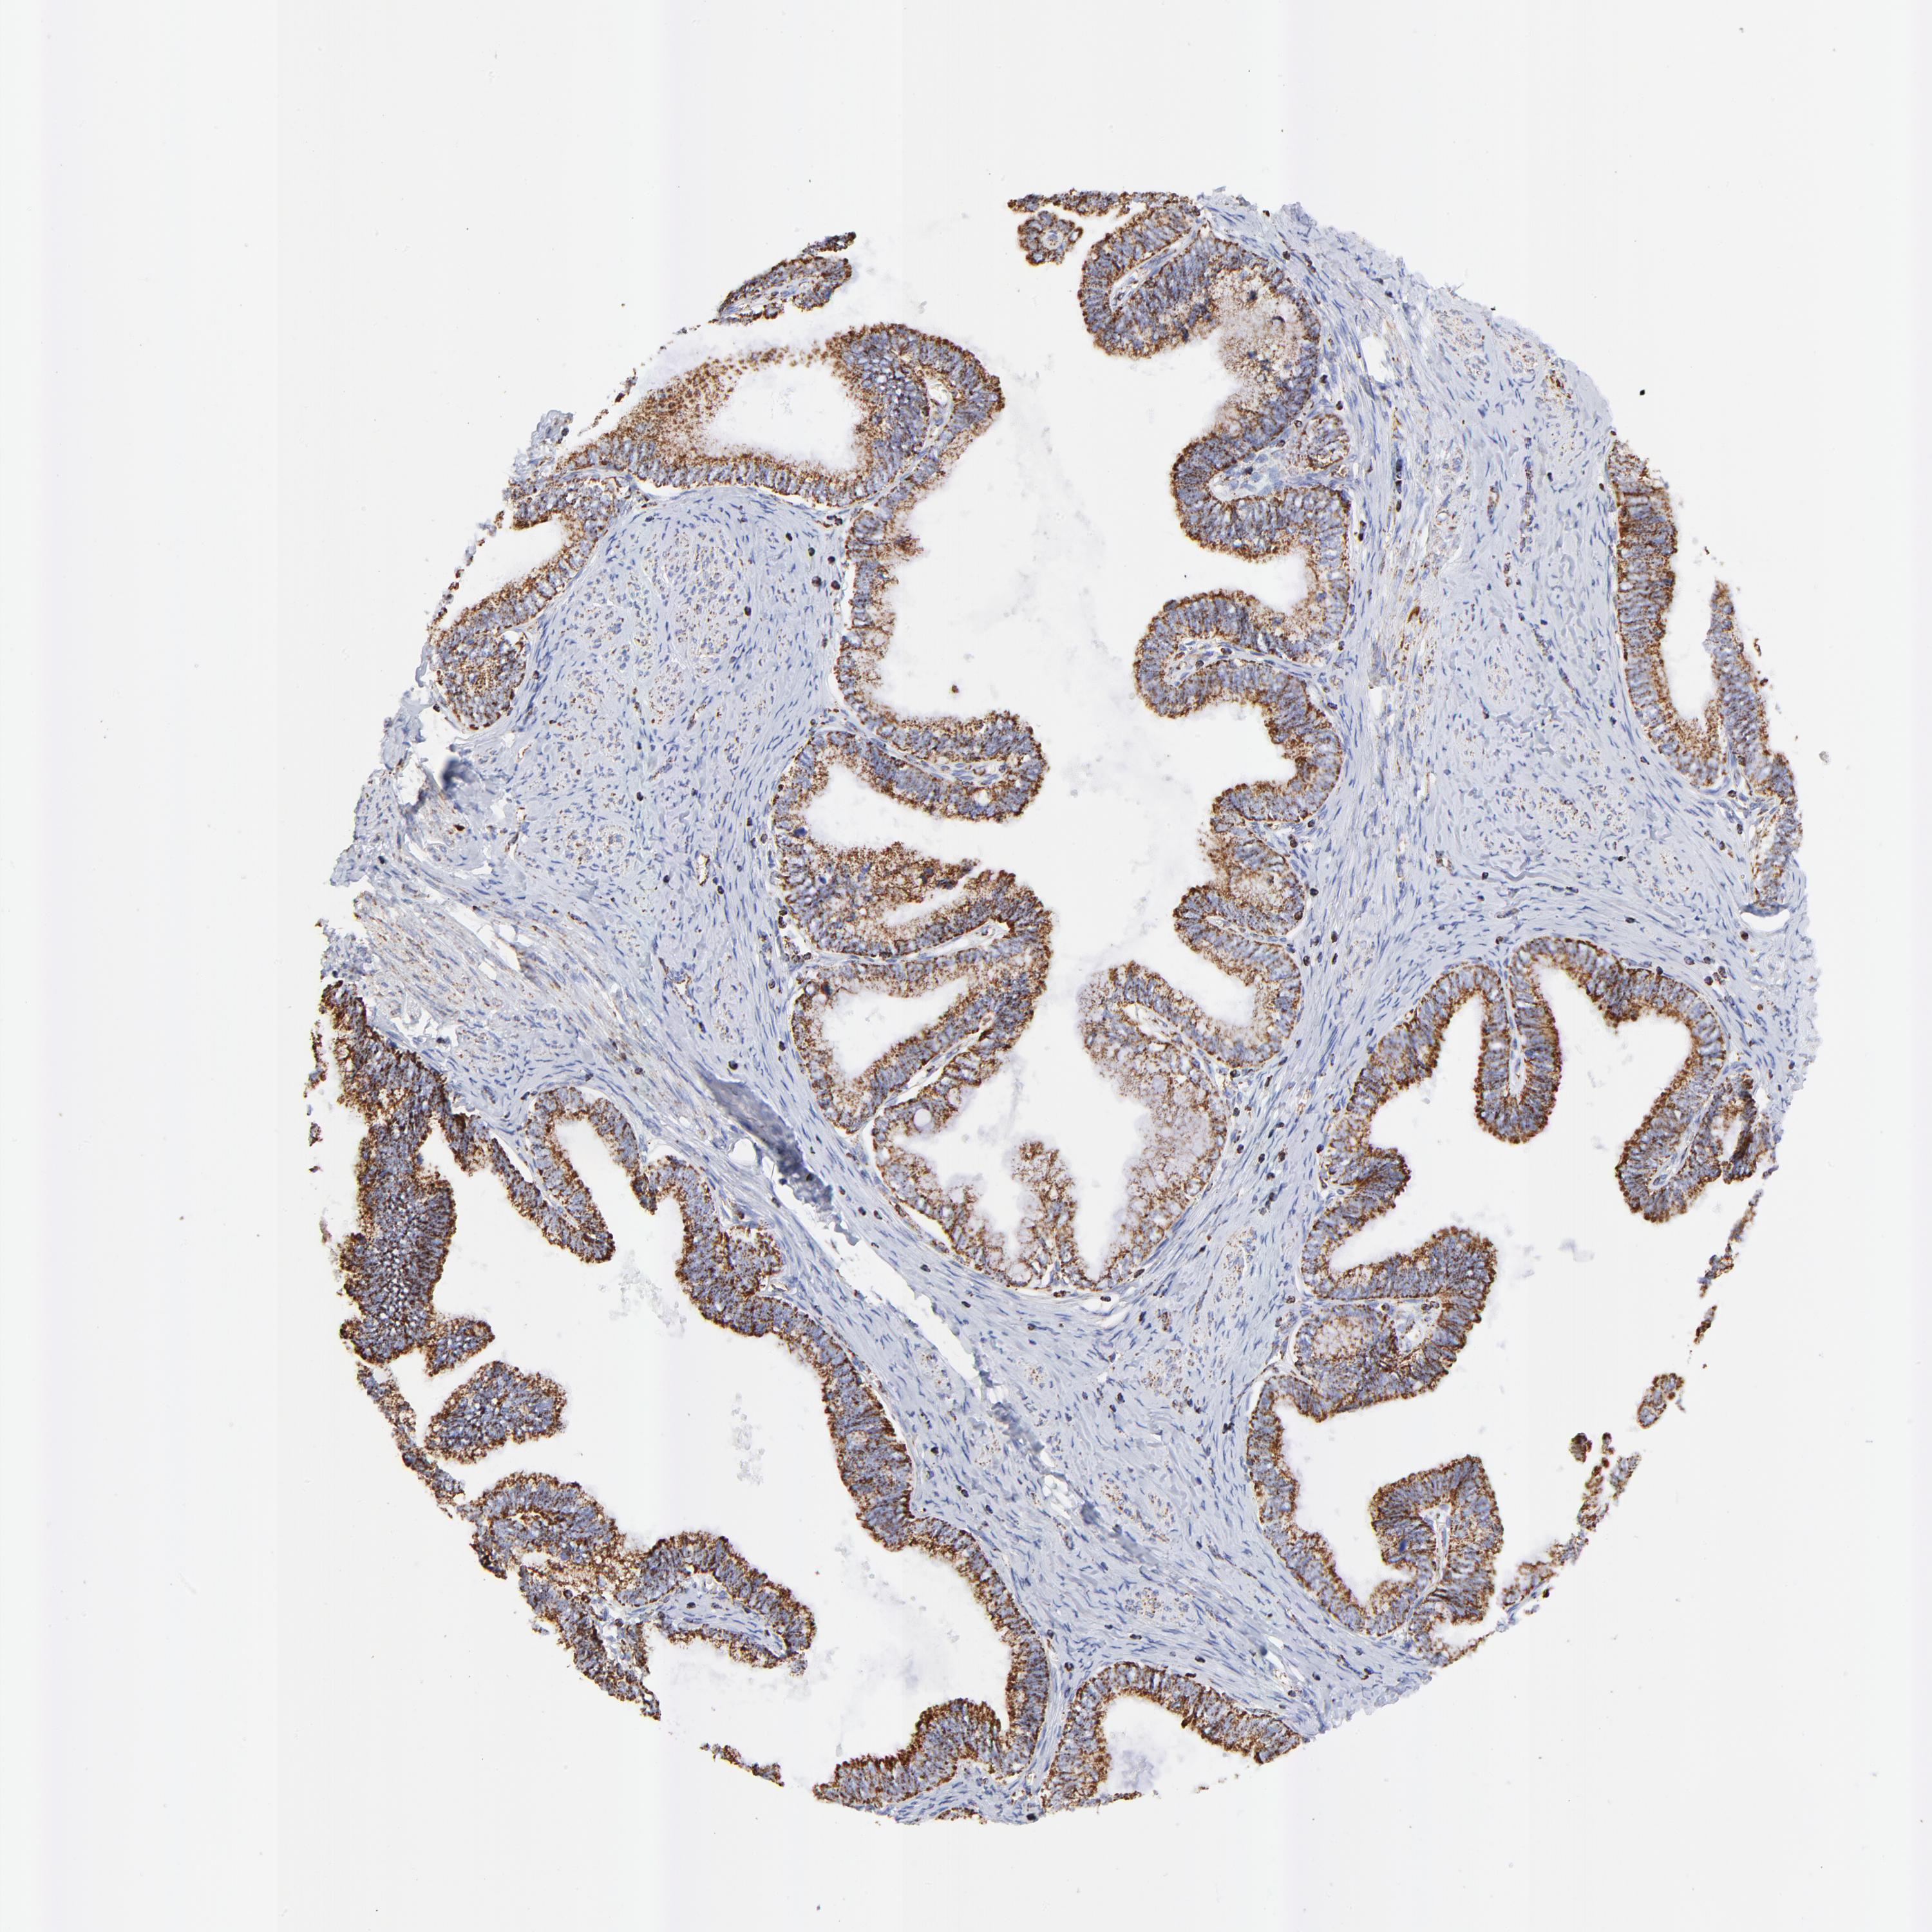

CERVICAL CANCER - Protein expressioni

A mouse-over function shows sample information and annotation data. Click on an image to view it in a full screen mode. Samples can be filtered based on level of antibody staining by selecting one or several of the following categories: high, medium, low and not detected. The assay and annotation is described here.

Note that samples used for immunohistochemistry by the Human Protein Atlas do not correspond to samples in the TCGA dataset.

Antibody stainingi

Antibody staining in the annotated cell types in the current human tissue is reported as not detected, low, medium, or high, based on conventional immunohistochemistry profiling in selected tissues. This score is based on the combination of the staining intensity and fraction of stained cells.

Each image is clickable and will lead to virtual microscopy that enables deeper exploration of all samples and also displays staining intensity scores, fraction scores and subcellular localization as well as patient and tissue information for each sample.

Antibody HPA002485

Antibody CAB004080

Staining

High

Medium

Low

Not detected

Intensity

Strong

Moderate

Weak

Negative

Quantity

>75%

75%-25%

<25%

None

Location

Nuclear

Cytoplasmic/membranous

Cytoplasmic/membranous,nuclear

Adenocarcinoma, NOS